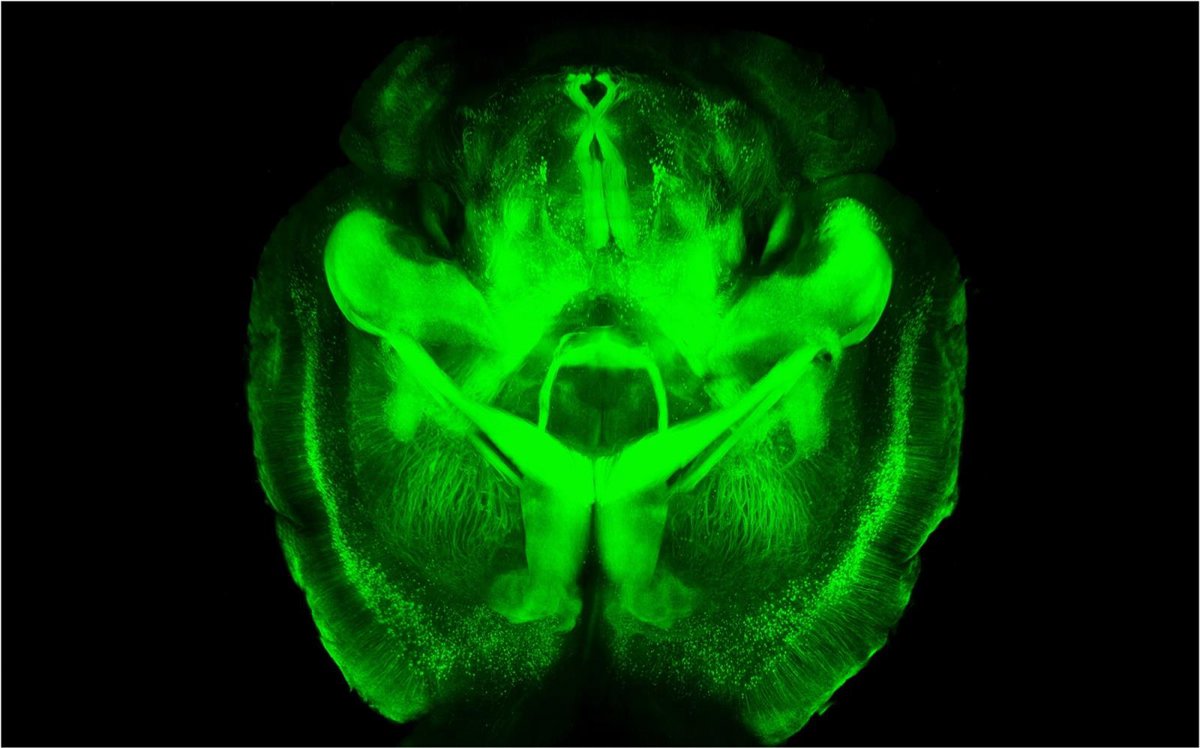

Cerebro transparente

STANFORD UNIVERSITY